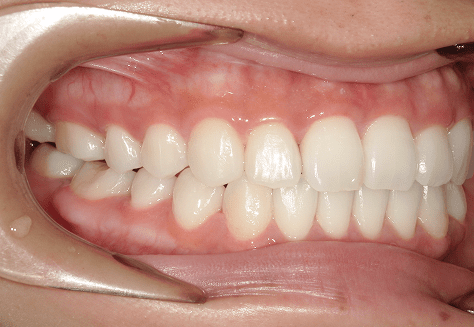

M.U

治療前

治療後

主訴

下の歯が特にガタガタなのが気になる。上の前歯が1本反対になっている。

診断

下顎前突・叢生・反対咬合

年齢/性別

20代/男性

抜歯部位

非抜歯

使用装置

上下インビザライン(PBM使用)

保定装置

ビベラリテーナー

料金

初回資料採得・・・・・・・30,000円

診断料・・・・・・・・・・33,000円

動的治療終了時資料採得・・5,500円 -

基本料金

950,000円

診察料金

5,500円×16回

治療期間

1年7カ月